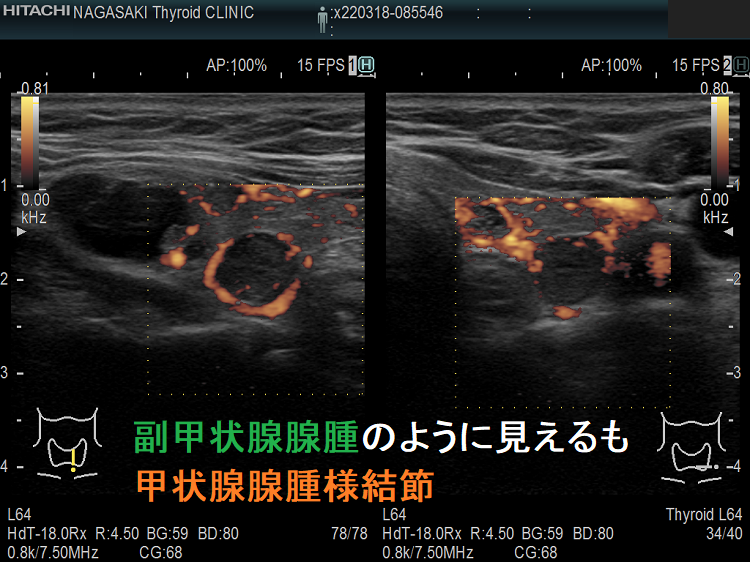

副甲状腺腺腫のように見えるも、実は排液後の甲状腺腺腫様結節

副甲状腺腺腫と同じような位置(写真では左甲状腺の背側)にあり、甲状腺の中なのか外なのかはっきりしません。副甲状腺腺腫のように見えるも、実は甲状腺の中にある甲状腺腺腫様結節。その他、排液後の甲状腺腺腫様結節も副甲状腺腺腫と同じように見える場合もあります。